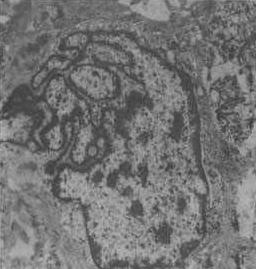

纖維肉瘤的顯微鏡圖片鏡下可見腫瘤由梭形成纖維細胞組成,交織成鏇渦狀,這些細胞可產生豐富的網狀纖維,有時也能產生粗膠原束。大多數皮膚纖維肉瘤分化良好,產生豐富的纖維組織,很少有絲分裂,未見明顯鏇渦狀結構,而產生纖維少,這些現象表明有侵襲性,預後較差。分化不好的腫瘤細胞有明顯的有絲分裂,但大而不規則的巨細胞或怪細胞則並不常見。腫瘤細胞可侵入血管壁內。分化更差的梭形細胞肉瘤,往往不能分清其組織來源。